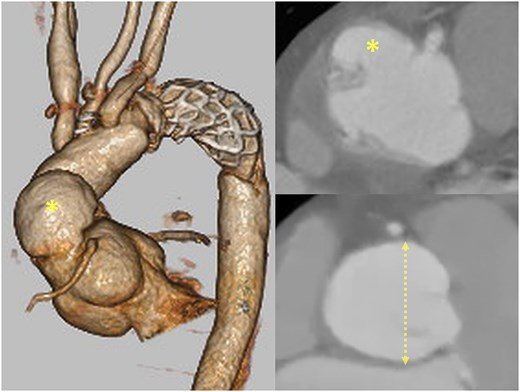

A 52-year-old man underwent emergency total arch replacement with a frozen elephant trunk for acute type A aortic dissection 1 year prior. Aortic root dilation (43 mm) and severe regurgitation were present at the initial event, but a supra-coronary replacement was selected. Follow-up imaging revealed enlargement of the root to 46 mm and a 37 × 23 mm proximal pseudoaneurysm (Fig. 1).

Preoperative CT showing the pseudoaneurysm (asterisk) and aortic root dilation (dotted line; 46 mm).